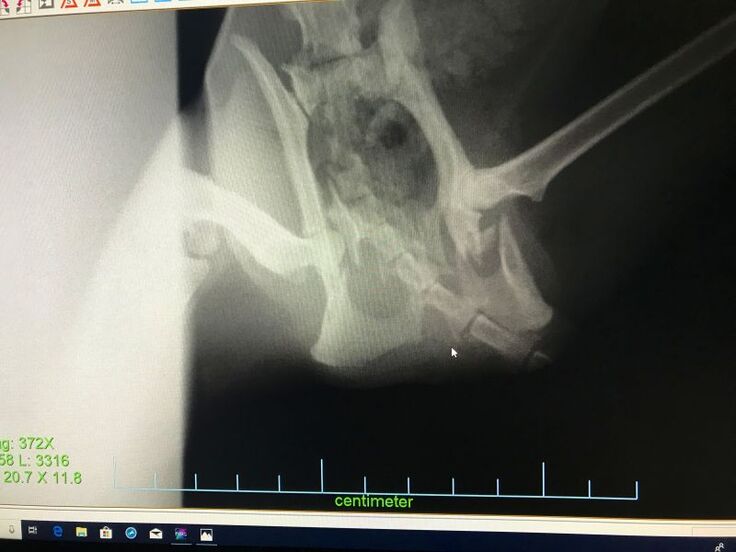

脚が立たないようなので仔猫2匹とクロちゃんを一緒に保護して動物病院で診察してもらうと、骨盤骨折していました。

初診のレントゲンでは骨盤の左側が骨折という診断で手術を受けましたが、手術後のレントゲンで右側も骨折していて、粉砕骨折しているという結果でした。

2回目の手術を受けて今はリハビリ中です。

交通事故に遭ったのだと思いますが、骨盤骨折して立てない動かない脚を前脚だけで引き摺って仔猫の元に帰ろうともがいて頑張って家の前まで帰って来ていたクロちゃん、なんとかうまく骨がつながって普通に歩いて走ってジャンプできるようになって欲しいと思います。

骨盤骨折しても必死で仔猫の元に帰えろうとしていたクロちゃんの骨盤骨折(粉砕骨折)を手術して元のように歩いて走ってできるようにしてやりたい。

長く待てないので、既に骨盤骨折の手術を2回受けました。

今は徐々に回復してヨタヨタしながらでも歩けるようになっていてリハビリ中です。